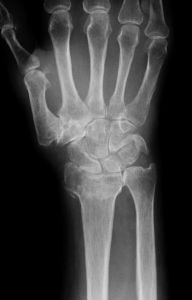

DIP関節症に対する関節固定術

PIP関節症に対する人工関節置換術

母指CM関節症に対する関節固定術(左)と関節形成術(右)

手指の関節痛の原因として多いのが、変形性関節症です。指には末梢からDIP, PIP, MP, CMという4つ(母指はIP, MP, CMの3つ)の関節があり、いずれも長年使い続ければ、徐々に軟骨がすり減り、骨が変形していきます。DIP(IP)関節に起こるものは『ヘバーデン結節』、PIP関節に起こるものは『ブシャール結節』と呼ばれることがありますが、それらを最初に文献に記した医師の名を冠したものです(ただし、レントゲン写真が発明される100年も前のことなので、実際には何を指しているのかは不明です)。母指のCM関節も変形が起こりやすく、手の機能障害の原因となります。

症状は、初期にはこわばり、強く曲げた時や押したときの関節の痛みが主ですが、進行すると関節の変形から可動性が障害されたり、骨破壊によって関節が不安定になることもあります。痛みは、必ずしも変形の程度と相関しません。関節の腫脹・発赤・疼痛など炎症の症状が強い場合には、リウマチと鑑別するために血液検査が必要です。

治療は、手指の安静が原則です。安静が保てれば、症状は自然に鎮静化することが多く、変形の急激な進行も予防できます。痛みが強い場合には、指の固定や関節内へのステロイド注入(当院ではおすすめしません)が行われる場合があります。変形が進行して、疼痛の強い関節、可動域が大きく損なわれた関節や高度に不安定な関節に対しては、症状を改善させるため、あるいは整容を目的として手術が行われることがあります。手術は、人工関節置換術を含めた関節形成術か関節固定術となります。